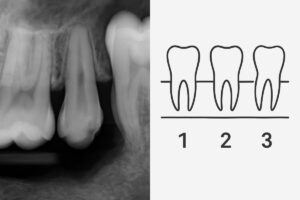

An implant molar is a three-part restoration: a titanium implant placed in the jawbone, an abutment that connects the implant to the crown, and a ceramic or porcelain crown shaped like a natural molar. Unlike a bridge, an implant molar replaces the tooth root as well as the visible tooth. That root replacement helps keep jawbone healthy and avoids trimming adjacent teeth.

Expect a consult with digital X-rays or 3D CBCT imaging to evaluate bone and nerve positions. Your provider will create a personalized plan and may recommend oral DNA testing or other diagnostics for complex cases.